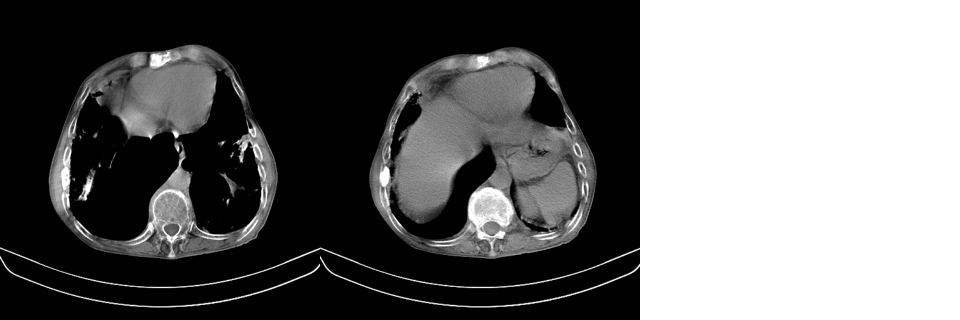

以下是引用mzh123在2007-8-26 19:58:00的发言:[br]两肺弥漫性斑片改变,其中可见大小不等之不规则空洞,结合既往病史还是考虑结核复发及感染。

以下是引用云翔在2007-8-26 20:54:00的发言:[br]这是44岁的肺吗?是否有先天病的基础?干酪性肺炎?